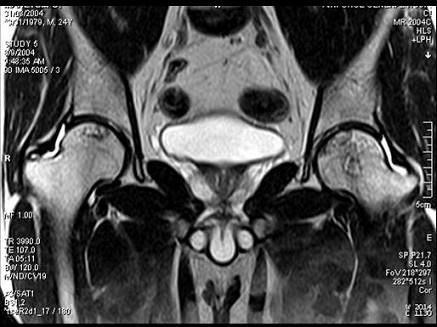

问题 患者,男,24岁,曾有外伤史,两侧髋部疼痛不适数月,请结合所提供的图像,选择最佳答案 ( )

选项 A、化脓性骨关节炎 B、类风湿关节炎两侧 C、髋关节退行性变 D、未见异常 E、股骨头无菌性坏死

答案 E